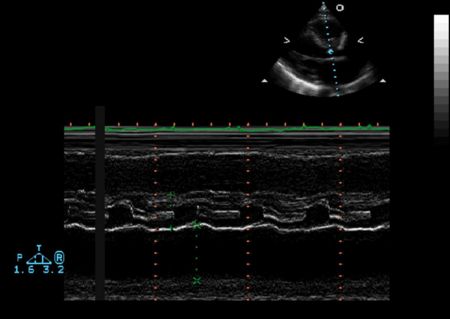

M Mode in Hypertrophic Cardiomyopathy

- Septal hypertrophy

- Systolic anterior motion (SAM) of the anterior mitral valve leaflet

- Mid-systolic (premature) closure of the aortic valve due to outflow track obstruction